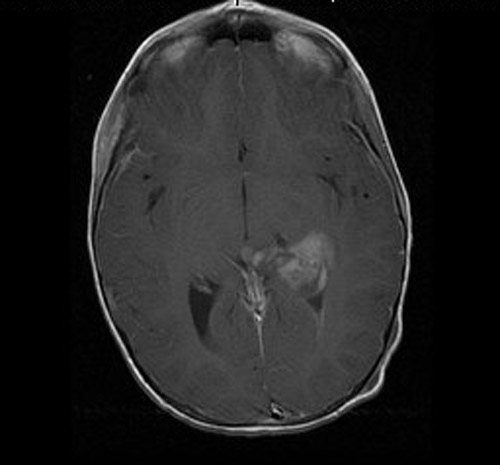

The patient was a 6 year-old girl who presented with a history of Streptococcal infection about 3 weeks ago and was treated with Amoxicillin. She improved briefly but started vomiting, hip pain, neck pain, and severe headache. She was treated with antibiotics under the impression of meningitis and she improved again. However, she started vomiting for several times again and was admitted to the emergency. An MRI scan demonstrated a brain mass as illustrated here. The lesion was excised and yielded this specimen.

• MRI studies demonstrate a 3.3 x 3.2 x 2.7 cm well-circumscribed mass in the left lateral ventricle. The tumor has both an exophytic part and parenchymal involvement of the underlying brain. This mass has heterogenous signal intensity on T1-weighed images and heterogeneous enhancement. On FLAIR images,  It causes a 0.5 cm midline shift to the right and mild dilatation of the right lateral ventricles. FLAIR images do not demonstrate excessive edema.

MRI T1

MRI T1 Contrast